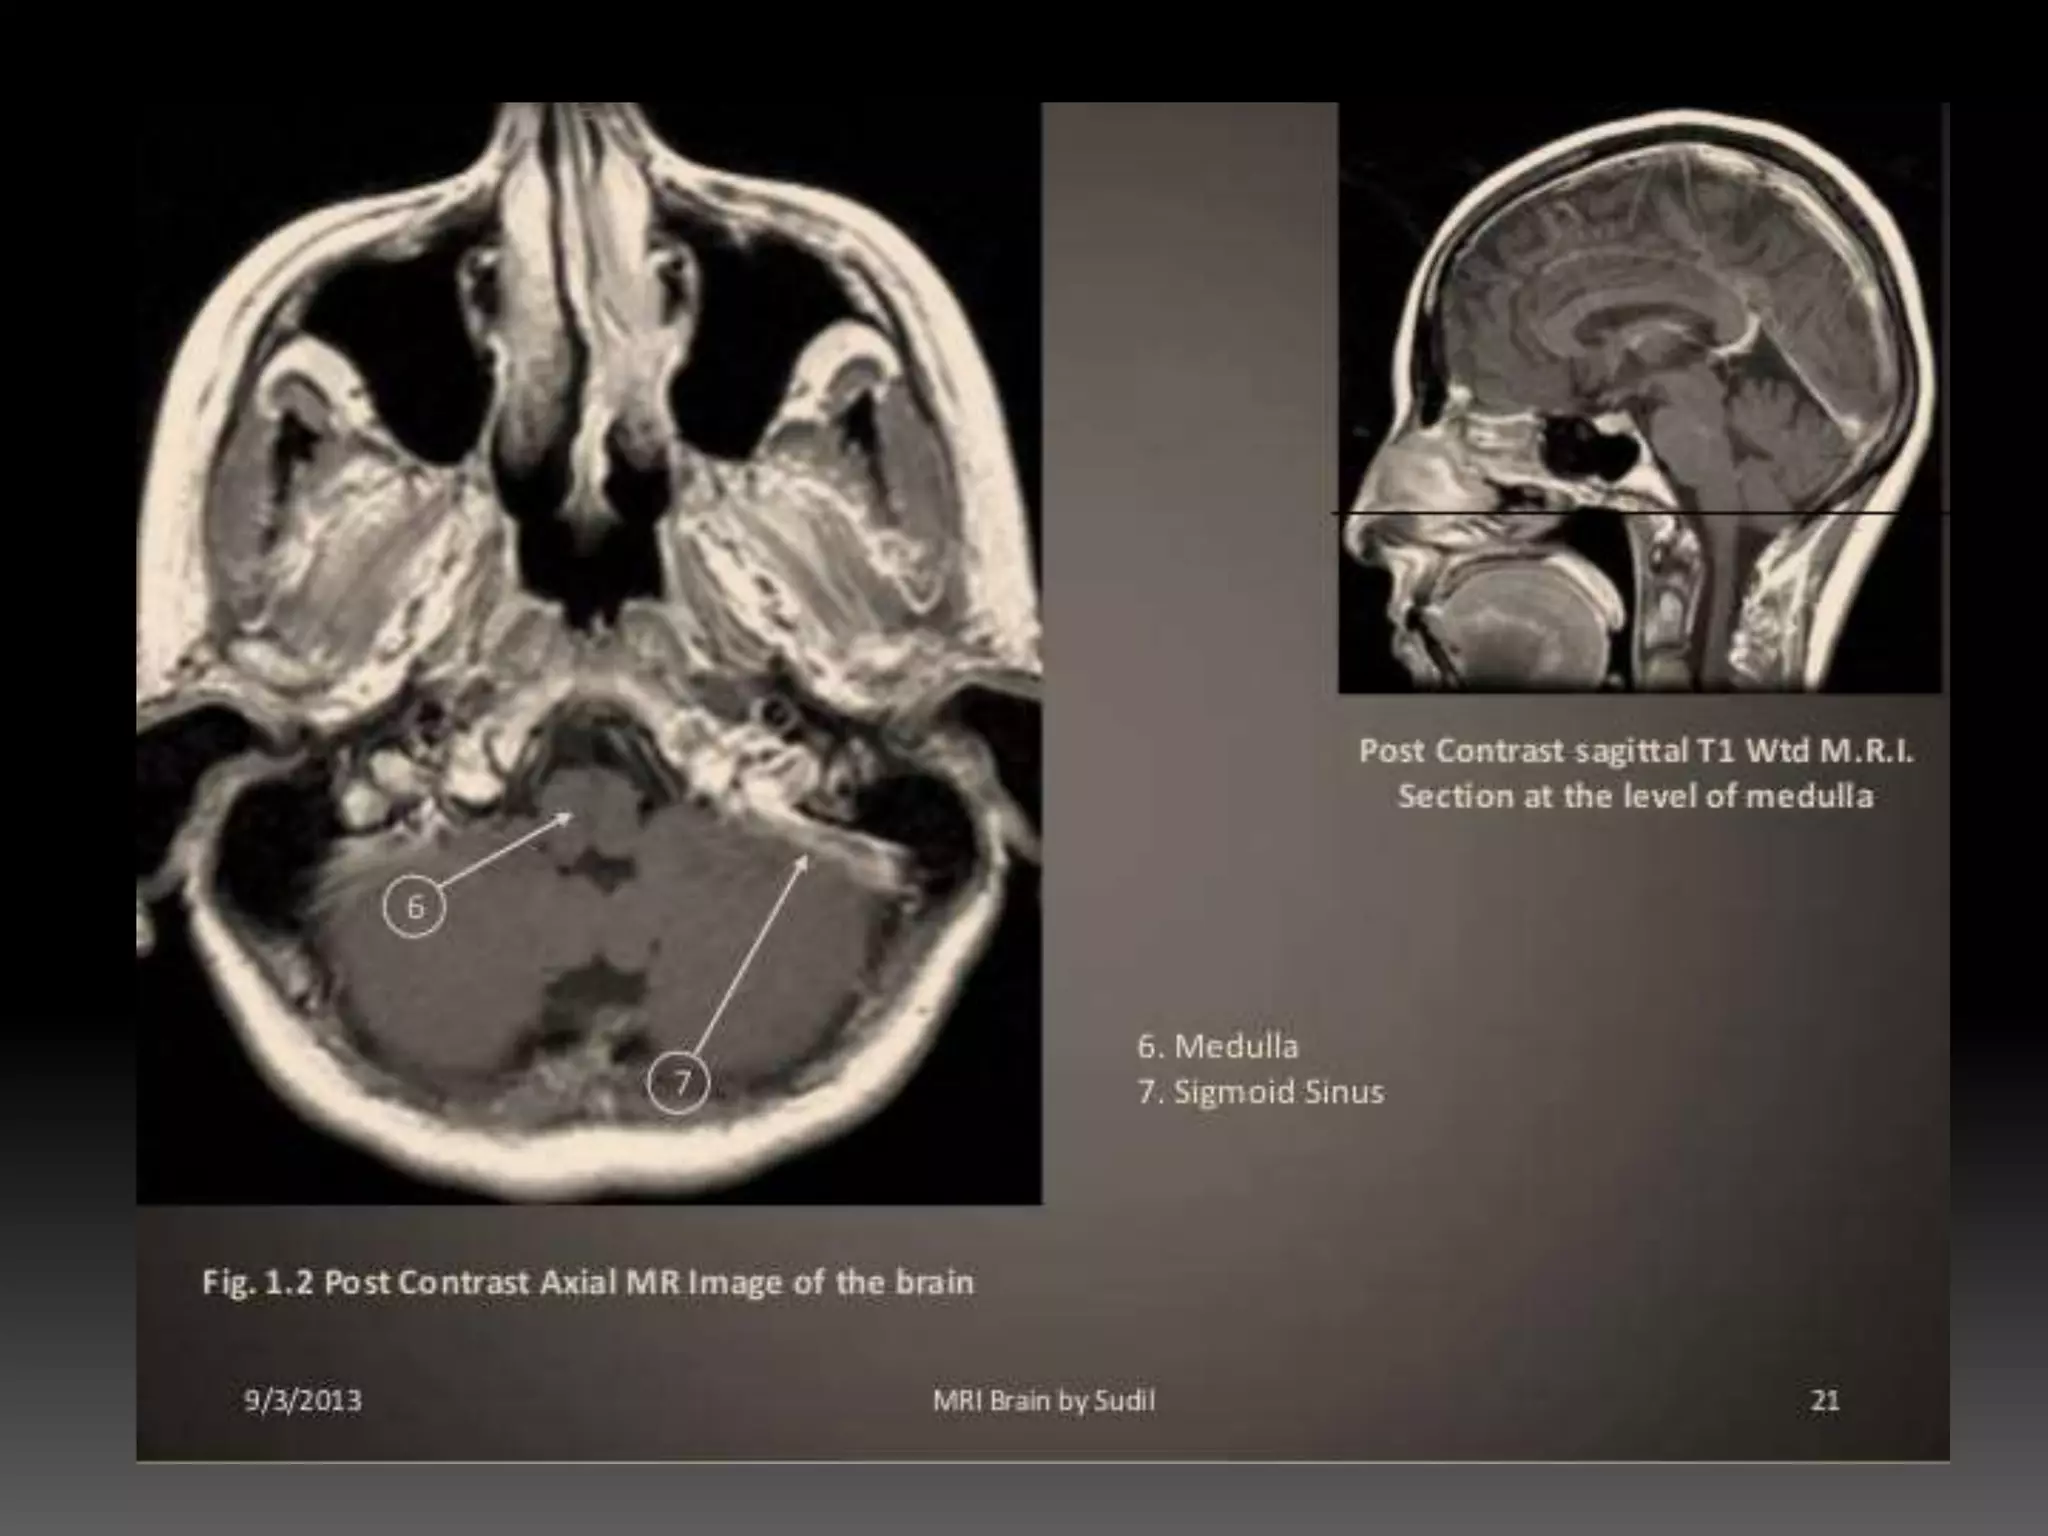

CONTRAST AGENTS • Gadolinium- administered intravenously to improve tissue contrast • It shortens the T1 relaxation times of enhancing tissues - making them appear brighter.